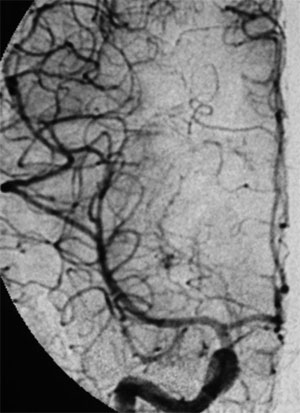

CASO 1 : Embolización de MAV frontal izquierda que presentó hemorragia cerebral resultando en hemiparesia derecha y trastorno del lenguaje

Angiografía antes del tratamiento por embolización. Se muestran por lo menos dos aneurismas en el interior del ovillo malformativo